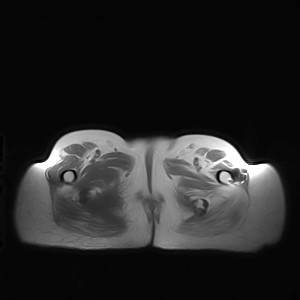

标题: MRI2691:读片病例2

我帮传的没看到病史!!!

图像太差了 1、右侧臀肌旁脓肿? 建议增强 2、左侧股骨头坏死并半脱位

1、左侧股骨头坏死并髋关节半脱位;

2、右侧臀肌感染,(可能褥疮所致)